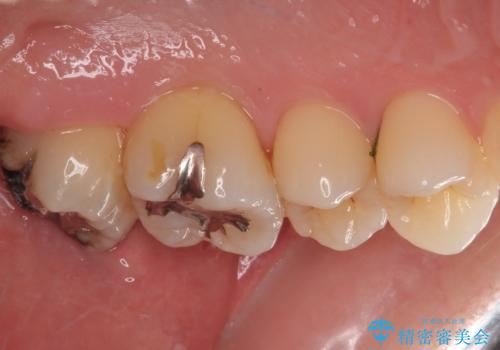

歯列が移動したとはいえ、左右ともに後方傾斜しており、むし歯の除去、形成(形を整える)、型取りの全てが非常に困難な処置となりました。

セラミッククラウンの適合はレントゲン写真からも分かる通り、境界がぴったりと合った、高適合のものとなりました。

矯正治療により処置が可能な位置に歯が移動したため、オールセラミッククラウンにて補綴治療を行うこととしました。